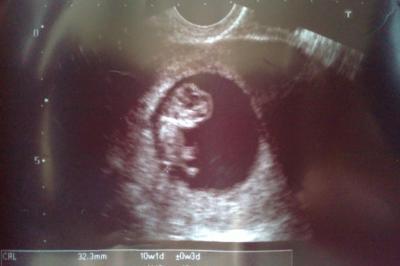

bei mir war das witzig... ich hab einen test aus der apotheke gemacht (hab extra die Apothekerin gefragt welcher gut ist) und der gab negativ (es war Mitte-Ende Oktiber) also dachte ich: schaaaadeeee haben es doch soooo lange versucht (zumal ich auch in Behandlung wegen PCO bin) also gut, kein problem, beim nächsten mal wirds was dann, kaum 2-3 Wochen später fing ich an mit enormer Übelkeit, Brechen und ganz leichten Blutungen nach GV... aber deine Mens. (seit 23 sep) also hab ich mir einen Termin bei meiner FA machen lassen... musste allerdigns voll lange warten und so kam ich Mitte Dezember auf den Tisch und sie hat einen US gemacht und siehe da schon in der 12ten SSW (anbei ein superscharfes und supersüßes US-Bild) Und wie wars bei euch gewesen??? Test, FA, oder erste Bewegungen ??? LG sabby 17+5

Bild zu Wie und wann habt ihr erfahren das ihr ss seit??? - Forum für Juni - Mamis

Das ist ja ein supersüßes Bild. Ich bin ganz verzückt Ich war zwar darauf vorbereitet, aber trotzdem ist es dann ne Überraschung, wenn der Test positiv ist. Hab mitte Oktober einen Test gemacht, der war negativ. 3 Tage nochmal einen und der war positiv. Hatte schon vorher nen Termin beim FA ausgemacht und der hat mir dann ne Woche später die SS in der 6. Woche bestätigt. Mir gings anfangs ziemlich schlecht. Darum haben wir es für uns behalten und der Familie und Freunden erst an Weihnachten gesagt. Eigentlich hab ich Wochenlang gar nicht so recht gewusst, was ich davon halten soll, wie ich mich verhalten soll. Und so recht genießen konnte ich es auch nicht wirklich. Erst seit ca. 3 Wochen geht es mir richtig gut und ich kann es genießen. Auch noch dem letzten US als man den Racker winken sah... LG